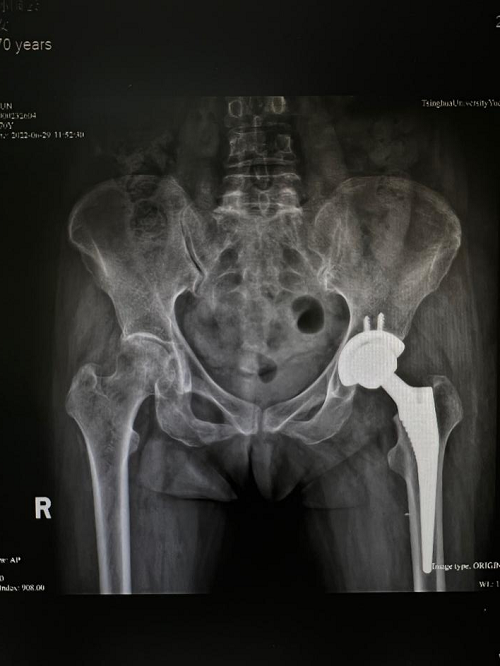

70岁的孙奶奶也成为了新政策的受益者。孙奶奶行走时不慎摔倒导致左髋部剧烈疼痛,无法站立和行走,家属急忙送到医院检查后发现是左侧股骨颈骨折。

包括股骨颈骨折在内的髋部骨折常被称为“人生最后一次骨折”,因为创伤对人体是一次打击,而很多老年人的基础情况较差,往往合并有慢性的心、肺疾病,如果保守治疗往往需要卧床休息。但长期卧床会引起肺部感染、褥疮等等并发症,严重时会危及老年人的生命。所以多等待一分钟,孙奶奶就多一分危险。对孙奶奶的身体进行详细检查后,第二天贾主任就给孙奶奶安排了人工全髋关节置换手术,手术十分顺利,孙奶奶术后第二天就可以在助行器辅助下站了起来。并在骨科进行了一周多的康复训练后顺利出院。